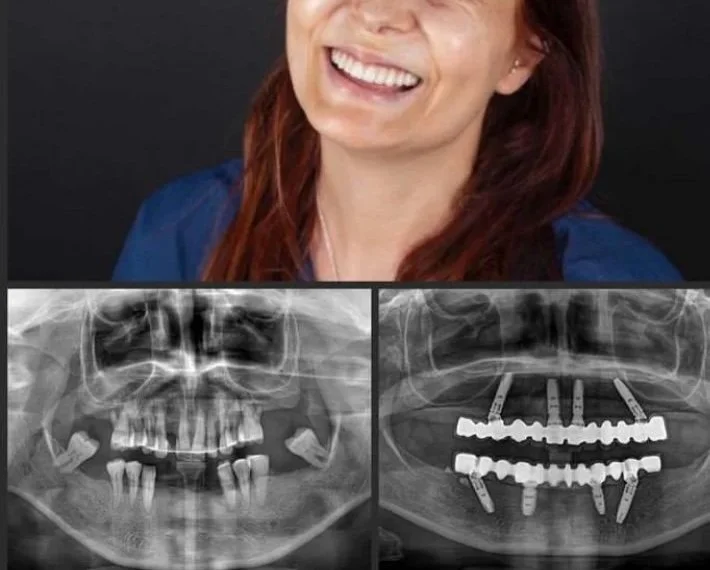

From preventive and cosmetic care to advanced implant surgery and oral rehabilitation — all delivered with precision, comfort, and care.

Dr. Onur Cavus is a general dentist with 20 years of clinical experience and doctoral training in Oral Surgery from Marmara University, Turkey.

He integrates advanced surgical expertise with comprehensive general and cosmetic dentistry — providing care that is precise, evidence-based, and patient-focused.

Certified in moderate IV sedation, Dr. Cavus ensures comfort and safety throughout every procedure, from single-tooth implants to full-arch rehabilitation.

Dental implants and All-on-4 full-arch solutions in Toronto and North York by Dr. Onur Cavus—implant surgery, IV sedation, and wisdom teeth care.